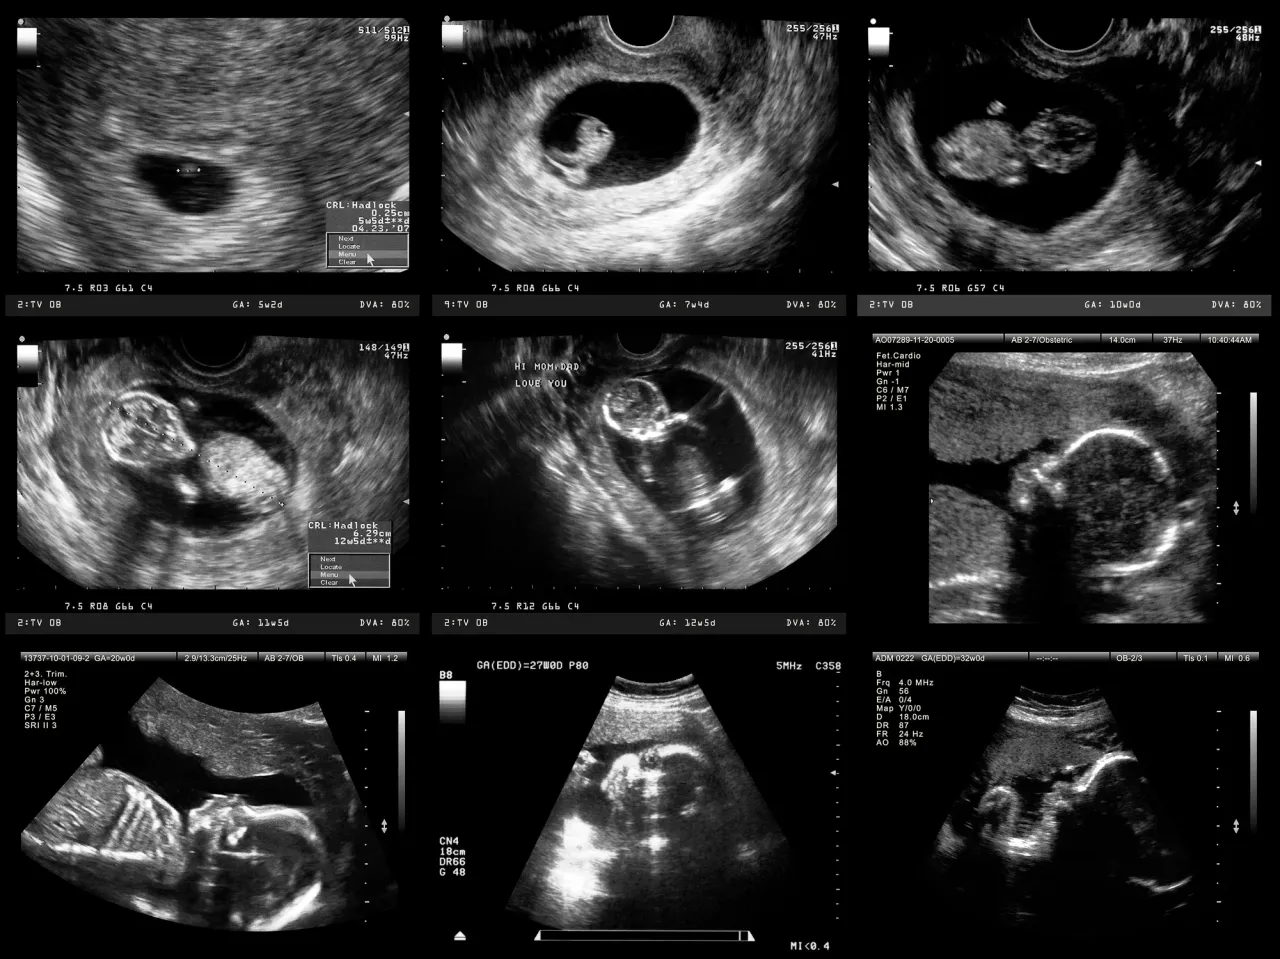

Pierwszy trymestr to czas intensywnego rozwoju i moment na wykonanie niezwykle ważnych badań przesiewowych. To właśnie wtedy możemy wcześnie oszacować ryzyko wystąpienia niektórych wad genetycznych i wrodzonych. Pamiętaj, że wczesna diagnostyka daje nam najwięcej możliwości działania.

USG genetyczne: kiedy dokładnie zapisać się na to najważniejsze badanie (11-14 tydzień)?

USG genetyczne, często nazywane przesiewowym USG I trymestru, to jedno z najważniejszych badań w całej ciąży. Jego wykonanie jest ściśle określone: powinno odbyć się między 11. a 14. tygodniem ciąży, a precyzyjniej między 11 tygodniem + 1 dniem a 13 tygodniem + 6 dniami. Dodatkowym warunkiem jest odpowiednia długość ciemieniowo-siedzeniowa (CRL) płodu, która powinna wynosić od 45 do 84 mm. Podczas tego badania lekarz szczegółowo ocenia przezierność karkową (NT) oraz obecność kości nosowej (NB). Te markery, w połączeniu z innymi parametrami, pozwalają oszacować ryzyko wystąpienia wad genetycznych, takich jak zespół Downa, Edwardsa czy Patau.

Drugi trymestr to okres, w którym płód jest już na tyle rozwinięty, że możemy bardzo szczegółowo ocenić jego anatomię. To czas na badanie, które dla wielu rodziców jest jednym z najbardziej wyczekiwanych USG połówkowe.

USG połówkowe (morfologiczne, II trymestru): dlaczego to badanie to absolutna podstawa i co pozwala wykryć?

Trzeci trymestr to czas, kiedy przygotowujemy się do porodu, a badania koncentrują się na monitorowaniu wzrostu i dobrostanu dziecka, upewniając się, że wszystko przebiega prawidłowo przed tym wielkim dniem.

USG III trymestru (28-32 tydzień): co lekarz ocenia na ostatniej prostej?

USG III trymestru to ostatnie rutynowe badanie ultrasonograficzne w ciąży, wykonywane zazwyczaj między 28. a 32. tygodniem ciąży. Jego głównym celem jest ocena tempa wzrostu płodu sprawdzenie, czy rozwija się on prawidłowo i czy jego masa odpowiada wiekowi ciążowemu. Lekarz ocenia również dobrostan płodu, ilość płynu owodniowego, lokalizację łożyska oraz, co jest bardzo ważne przed porodem, ułożenie dziecka. To badanie pozwala wykryć ewentualne późno ujawniające się wady rozwojowe lub komplikacje, które mogą mieć wpływ na przebieg porodu.